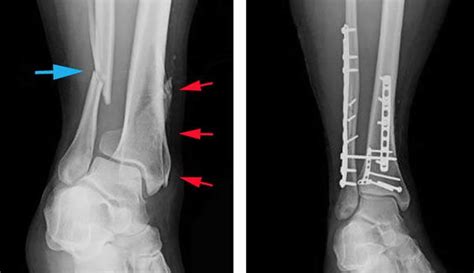

Ankle Fractures Diagnosis and Treatment - Eazy foot